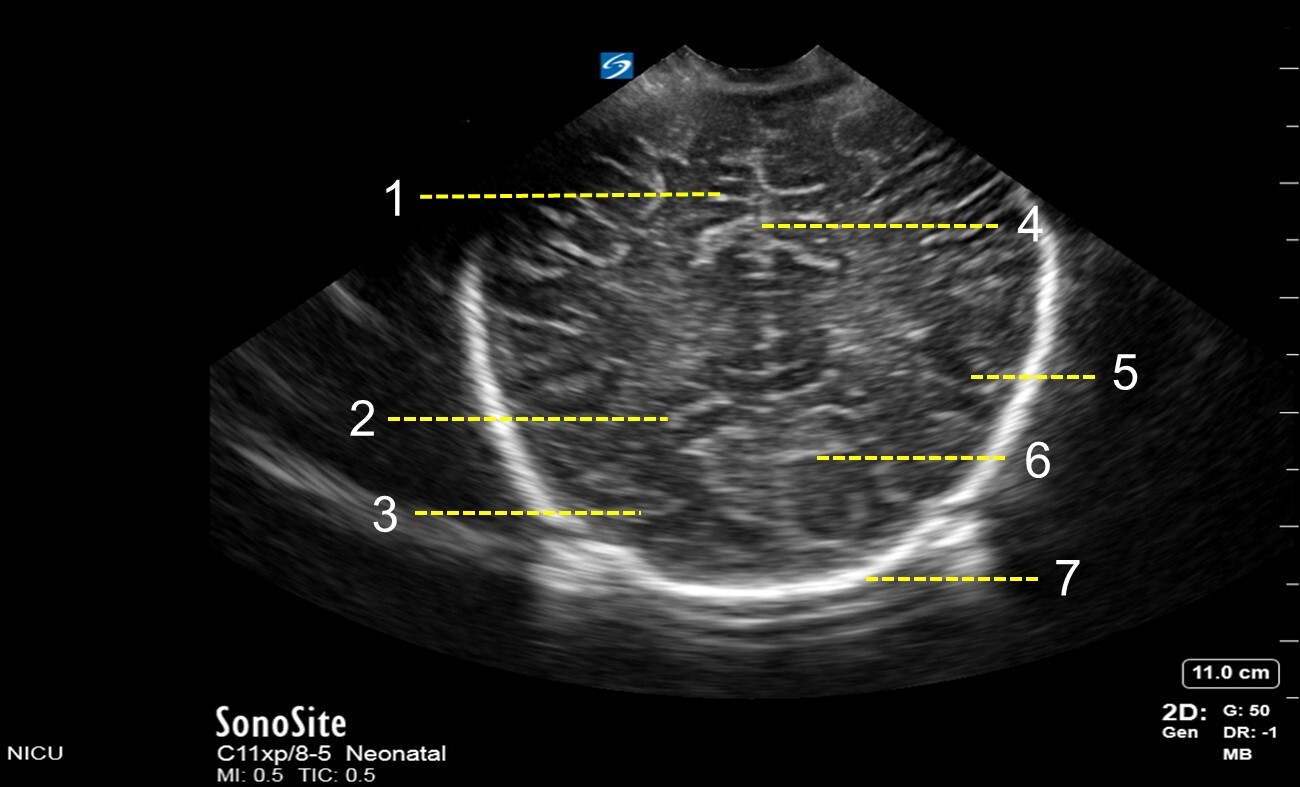

1. Cingulate Sulcus

2. Parieto-occipital Fissure

3. Occipital Lobe

4. Interhemispheric Fissure

5. Parietal Lobe

6. Calcarine Fissure

7. Skull